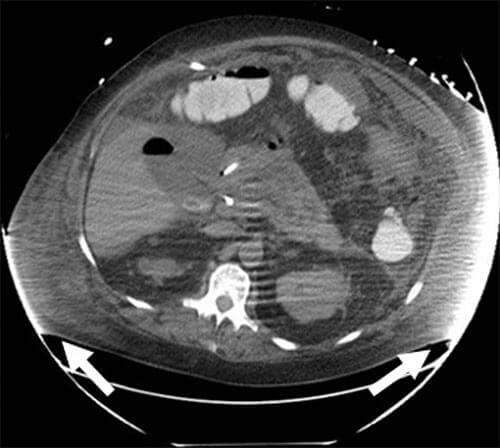

If part of a patient’s anatomy extends to the edge of the CT gantry, this can result in beam hardening artifact, which appears as alternating streaks of white and dark lines within adjacent tissues. Beam hardening artifact may obscure findings and limit interpretation of the image.

Axial CT slice showing multiple CT artifacts related to size, including increased noise/quantum mottle throughout the image, beam hardening artifact at the flanks (arrows), and motion artifact, which manifests as indistinct organ margins.1